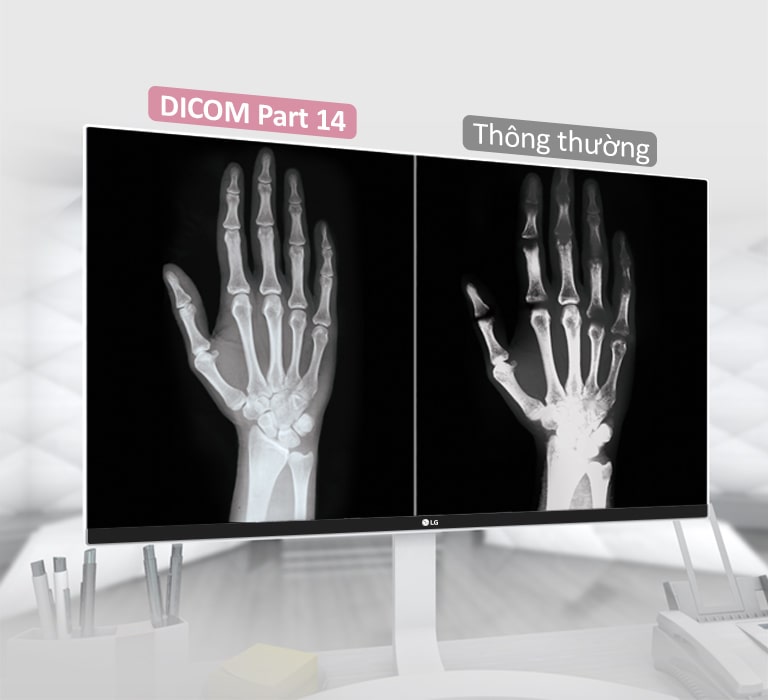

Tương thích DICOM

CÓ